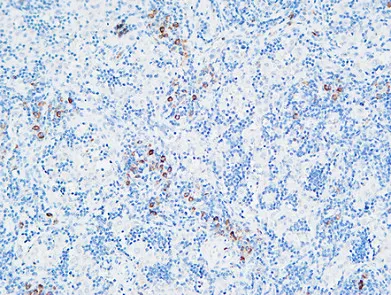

FOXP1 Rabbit Polyclonal Antibody

Cat: APRab11113